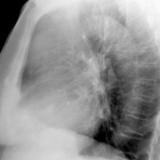

Case 8b Thymoma Lat